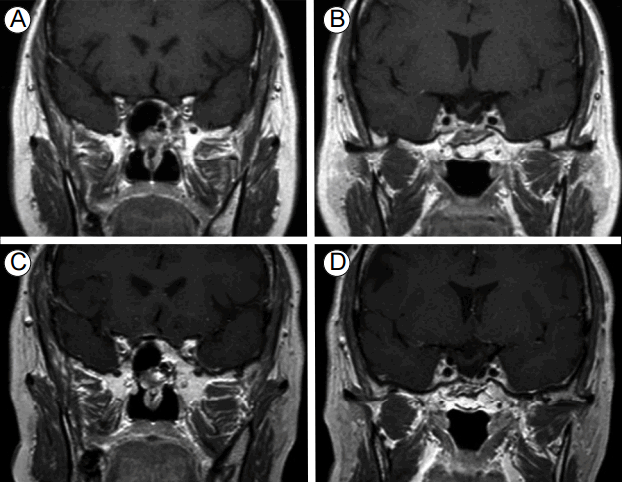

Figure 1.

(A, B) Magnetic resonance imaging (MRI) of the sella at the time of the first diagnosis. Pituitary macroadenoma (3.0 × 2.1 cm) with invasion of the right cavernous sinus. (C, D) MRI of the sella after the first operation. Only subtotal removal of the pituitary tumor was achieved; residual tumor is seen in the right cavernous sinus (arrow).